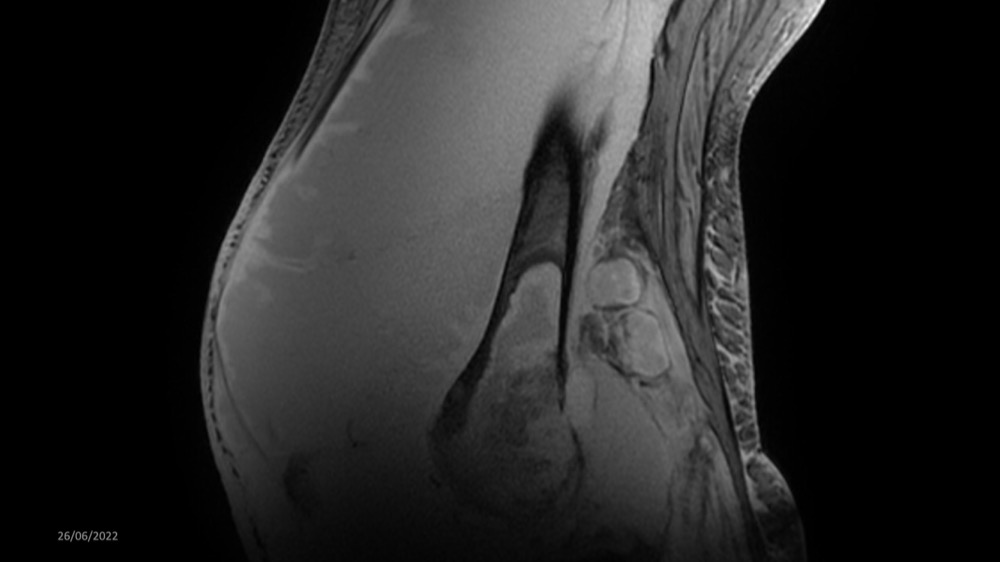

Reichert / Amar / Tordjman / Carlier 29/06/2022